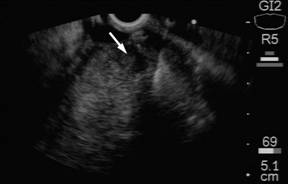

On the following abdominal CT scans performed between 90 and 95 months of follow-up, gradual enlargement of the pancreatic head with the suspicion of a tumor was noted (Figure 4). This was confirmed by both endoscopic ultrasound (Figure 5) and 11C-acetate PET/CT scan (Figure 6). Moreover, microscopic examination of the fine-needle aspirate of the pancreatic head tumor obtained during endoscopic ultrasound showed the presence of atypical hepatocytes within the tumor. In view of this, the patient was accepted for surgical treatment again and pancreaticoduodenectomy with the �uncut Roux� reconstruction was successfully performed at 97 months since the initial surgery. The pathologic examination revealed the diagnosis of a metastatic fibrolamellar hepatocellular carcinoma of the head of the pancreas. The postoperative course was uneventful and the patient did not experience recurrence within the last 18 months after pancreaticoduodenectomy. Following five laparotomies and one thoracotomy for fibrolamellar hepatocellular carcinoma and its recurrences, the patients remains well at the overall follow-up of 114 months at present.

Figure 5. Endoscopic ultrasound of the pancreatic head tumor (arrow). |

|

Figure 6. 11C-acetate PET/CT scan showing a decreased uptake of the tracer within the pancreatic head (arrow) as compared to the remaining pancreatic tissue suggesting the presence of a pancreatic head tumor. |